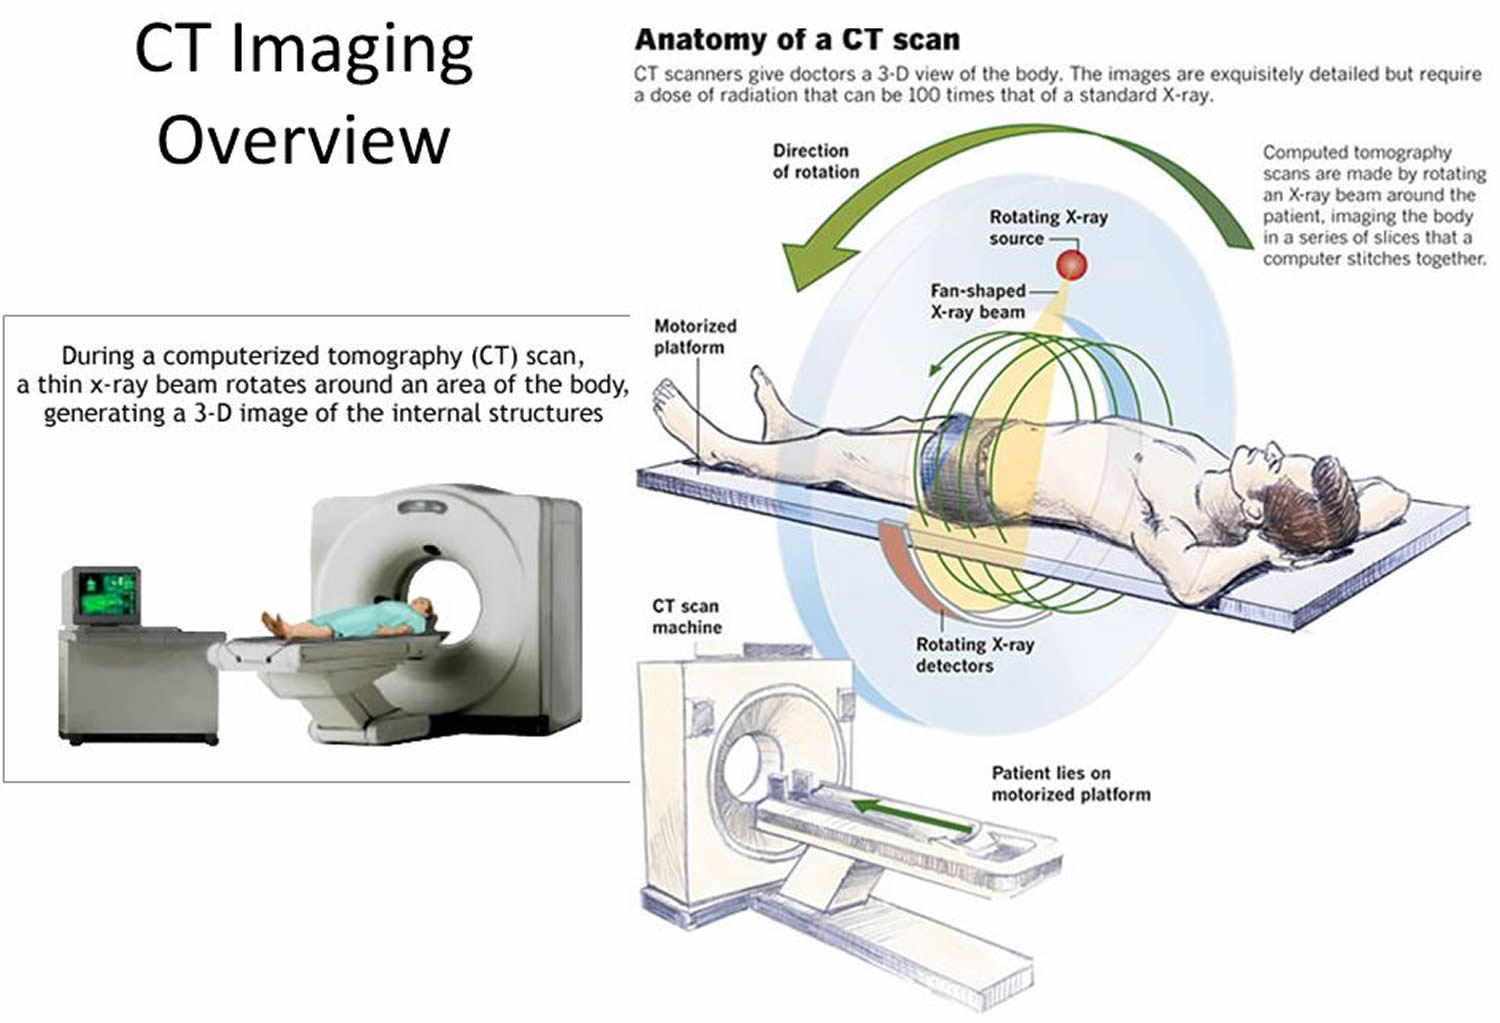

What Are CT Scans And How Do They Work? | Live Science

www.livescience.com

www.livescience.com

tomography scans computerized diagnose

CT Scan - Definition, Uses And Procedure

healthtian.com

healthtian.com

ct scan cat procedure technique definition body machines use ray uses share